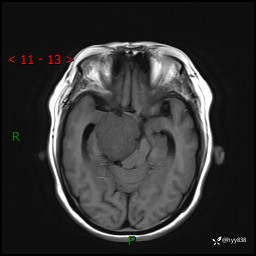

颅脑MRI平扫+增强